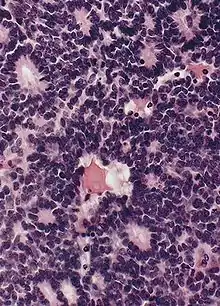

Flexner-Wintersteiner rosettes

• Tumor cells form Flexner-Wintersteiner rosettes